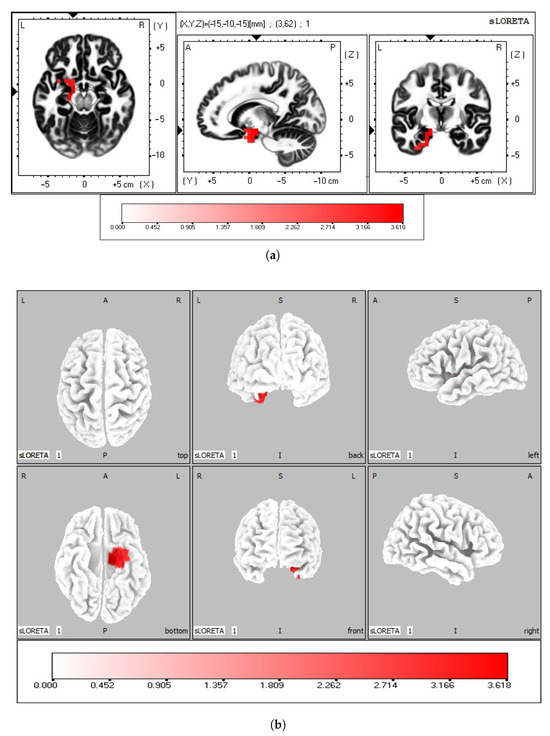

| Brodmann Areas | Structure | Lobe | Number of Voxels | p-Values |

|---|---|---|---|---|

| 20, 28, 34, 36, 38 | Uncus | Limbic | 29 | 0.0178 |

| 28, 34, 35, 36 | Parahippocampal gyrus | Limbic | 23 | 0.0134 |

| 13 | Insula | Sub-Lobar | 12 | 0.0178 |

| 20 | Inferior Temporal Gyrus | Temporal, Limbic | 4 | 0.0178 |

| 34 | Subcallosal Gyrus | Frontal | 3 | 0.0178 |

| 13, 21 | Sub-Gyral | Temporal | 2 | 0.0228 |

| 38 | Superior Temporal Gyrus | Temporal | 2 | 0.0228 |

| Structure | Brodmann Area | MNI Coordinates | ||

| x | y | z | ||

| Uncus | 34 | −15 | −5 | −25 |

| Parahippocampal gyrus | 28 | −15 | −10 | −15 |

| Insula | 13 | −35 | 5 | 15 |

| Inferior Temporal Gyrus | 20 | −30 | −5 | −45 |

| Subcallosal Gyrus | 34 | −25 | 5 | −15 |

| Sub-Gyral | 13 | −40 | 0 | −10 |

| Superior Temporal Gyrus | 38 | −35 | 5 | −15 |